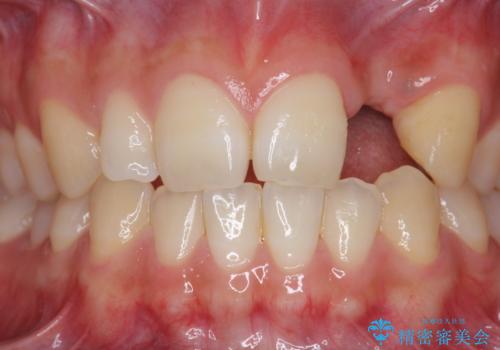

- 前歯の永久歯が元々なく、乳歯を失ったタイミングで前歯の審美性の回復を求めて来院されました。

機能・審美性の回復手段として、インプラント治療・ブリッジ・部分床義歯が考えられます。

それぞれの治療に特徴がありますが、取り外しの必要がなく隣の歯を削る必要も必要ないインプラント治療を選択されました。

前歯部にインプラントを埋入し、きれいに仕上げるためには骨の造成技術や歯肉の厚みを増すような処置を行い、インプラント周囲の環境を整備することが肝要です。